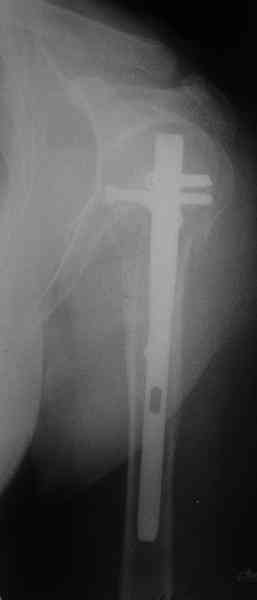

Another option could be closed nailing, see an example, the surgery was

done 2 days ago. In common such surgeries are performed under regional

anesthesia, not general.